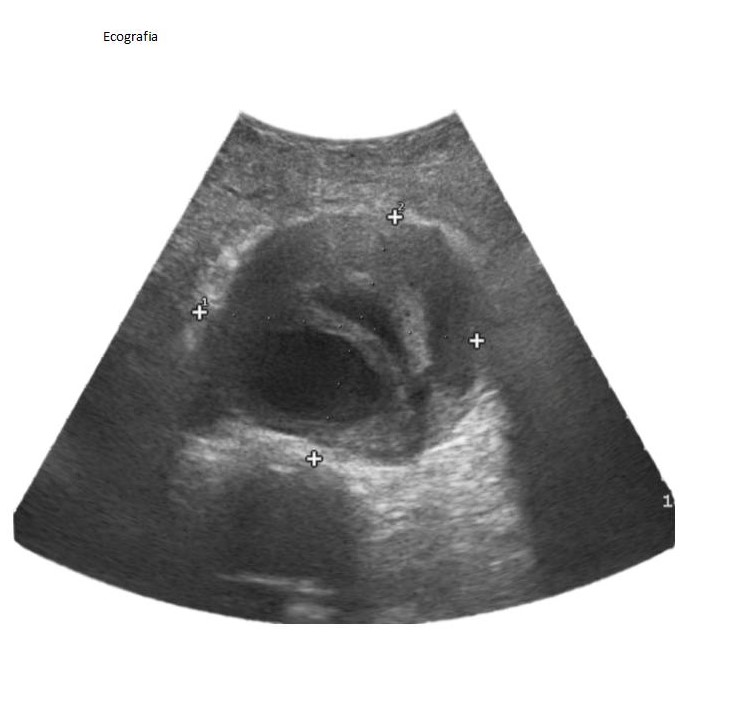

Ecografía en consulta: se observa aorta abdominal aumentado de tamaño > 8 cm.

Es derivado al servicio de urgencias.